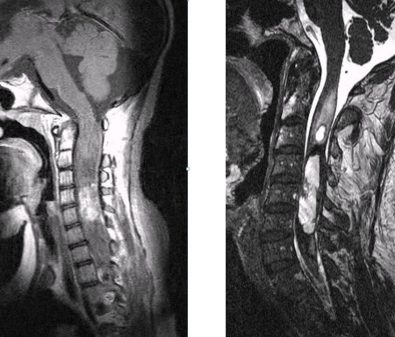

Οι ενδομυελικοί όγκοι αναπτύσσονται εντός του νωτιαίου μυελού (Εικόνα 1). Η συχνότητά τους σε σχέση με τους υπόλοιπους όγκους νωτιαίου μυελού είναι 5%. Τα αστροκυττώματα (στα παιδιά κυρίως) και τα επενδυμώματα (στους ενήλικες κυρίως) είναι οι συχνότεροι τύποι. Λιγότερο συχνοί τύποι είναι τα αιμαγγειοβλαστώματα, σηραγγώδη αγγειώματα και τα λιπώματα.

Οι ενδοσκληρίδιοι-εξωμυελικοί εντοπίζονται εντός της σκληράς μήνιγγας (δηλαδή του περιβλήματος του νωτιαίου μυελού) αλλά εκτός του νωτιαίου μυελού (Εικόνα 2). Η συχνότητα είναι περίπου 40% των όγκων σπονδυλικής στήλης. Οι πιο συχνοί τύποι είναι τα μηνιγγιώματα, τα επενδυμώματα του τελικού νηματίου, τα σβαννώματα και τα νευρινώματα. Πρόκειται στην πλειοψηφία τους για καλοήθεις όγκους.